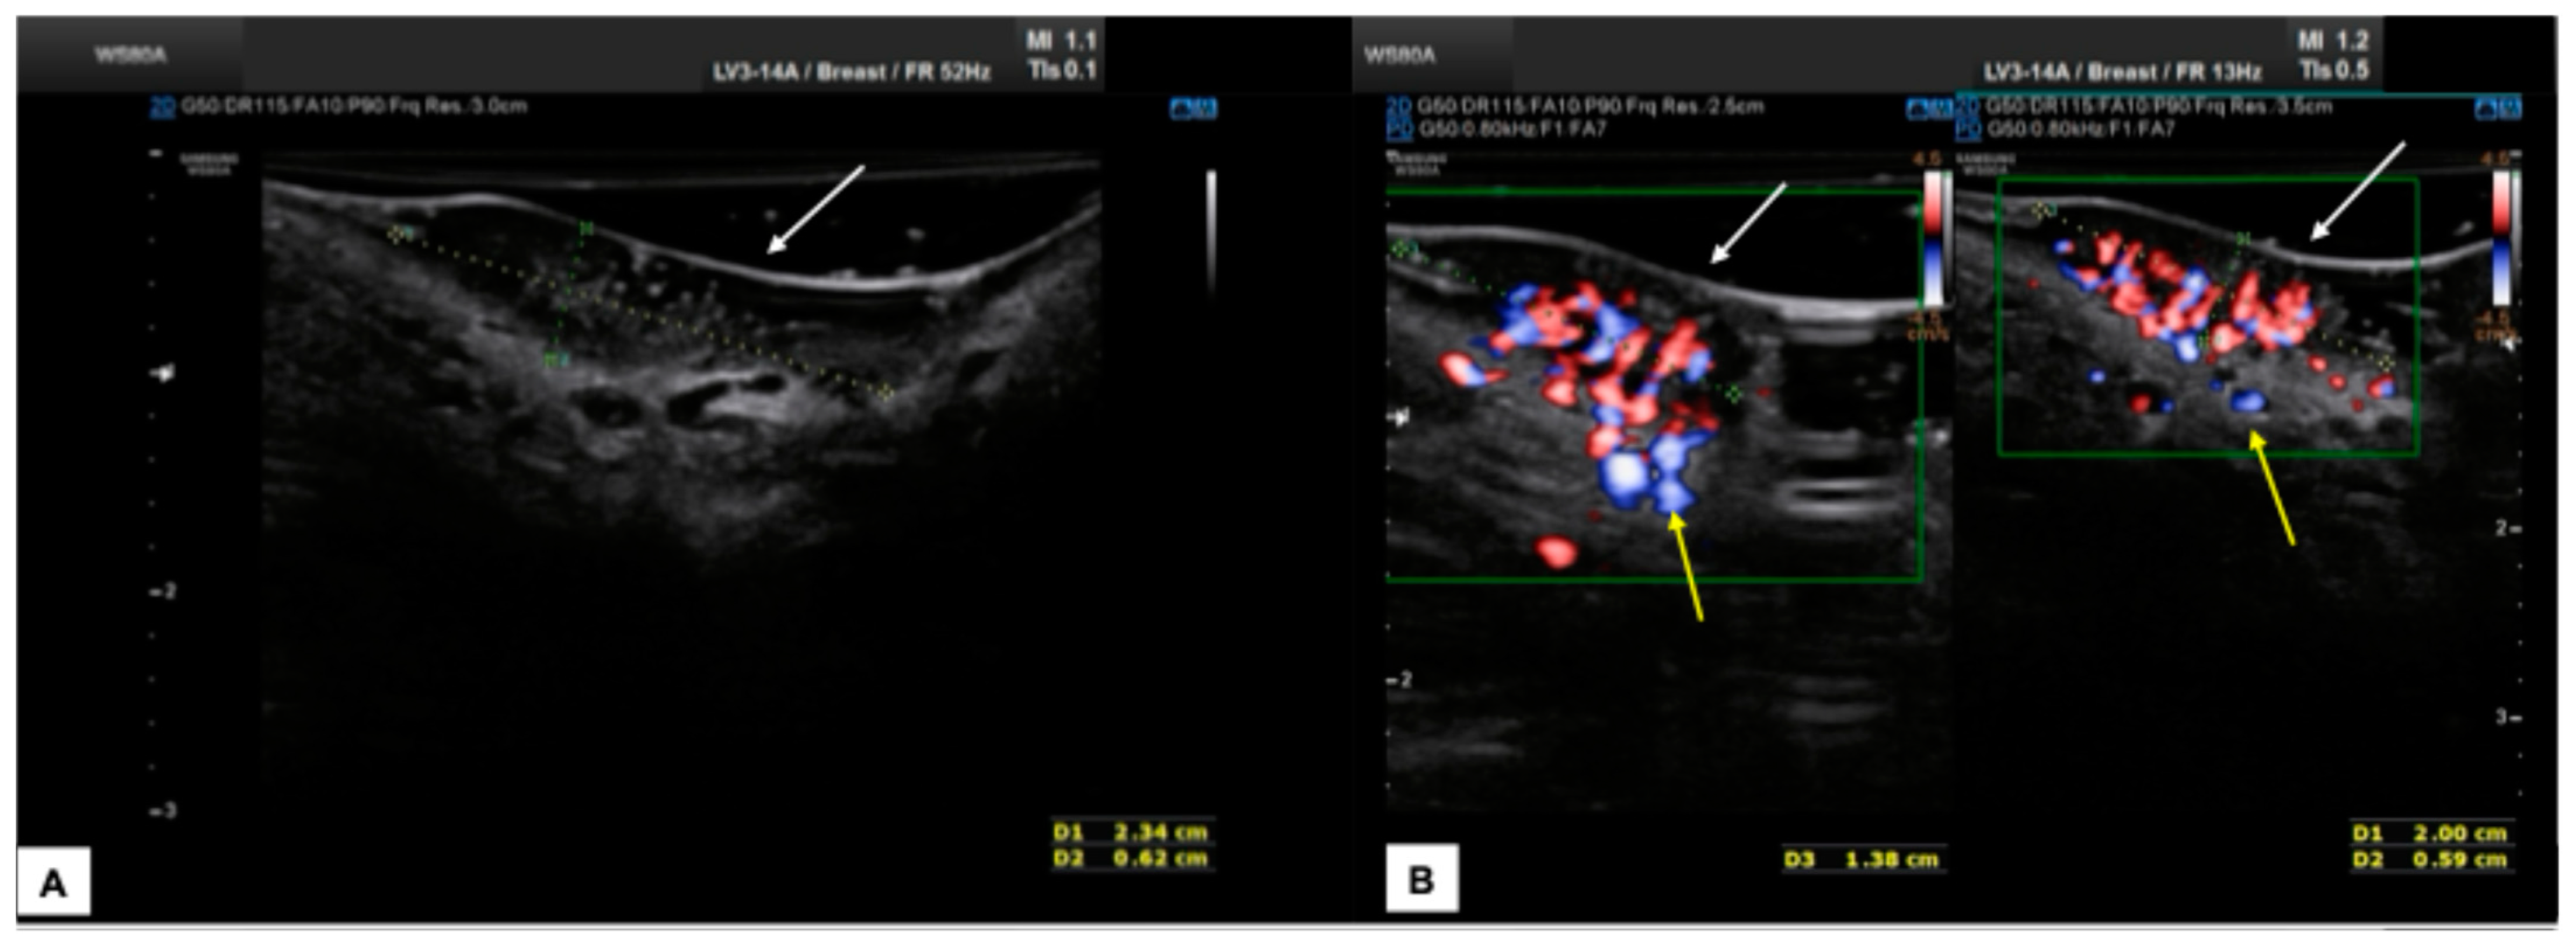

7.3. Malignant Vulvar Lesions